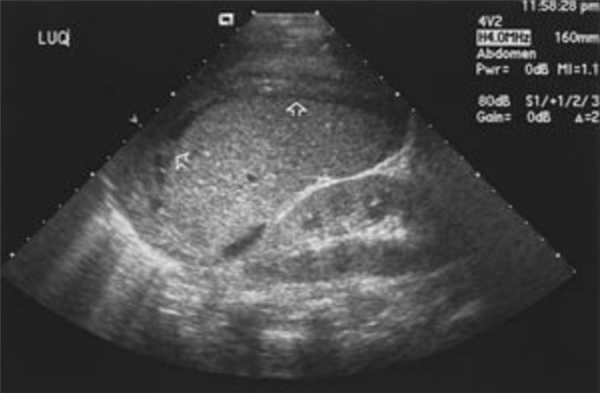

Обследование желудка при УЗИ брюшной полости

Ультразвук легко визуализирует внутренние органы, также можно рассмотреть полые органы, если обеспечить их наполнение жидкостью. Основными препятствиями для качественного обследования являются воздух и жир — эти особенности важно учитывать при подготовке к процедуре.

- Желудок.

В процессе УЗИ доктор может оценить габариты, положение, форму, плотность структуры органов и толщину их стенок, способность протоков и сосудов пропускать физиологические жидкости (желчь, секрет, кровь, мочу), наличие камней, состояние желчи. По итогам обследования выдается результат в виде снимков и их расшифровки.